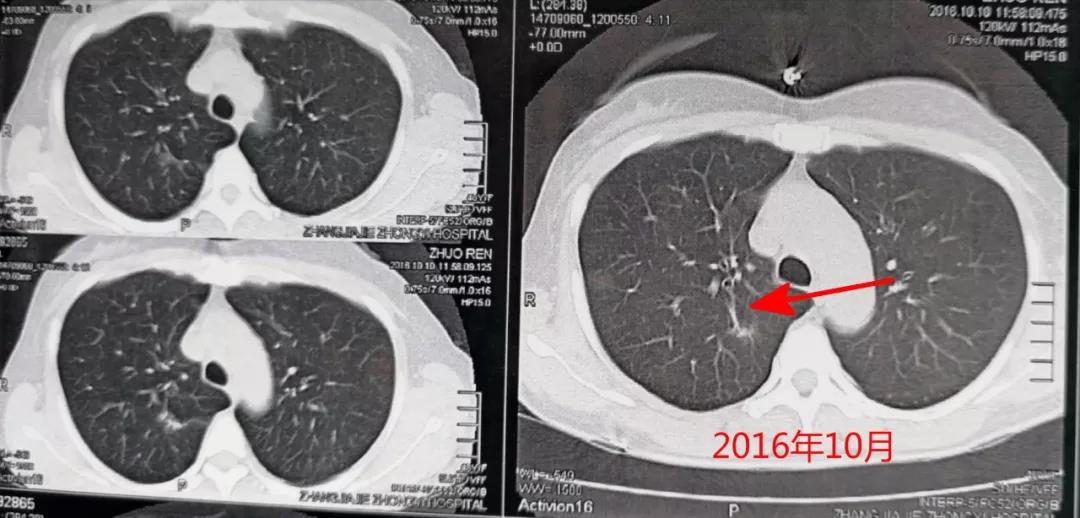

下麵這張圖是患者初次髮現結節時的CT圖:

整整一年,右上肺結節進行性增大,如下圖:

很顯然瞭,從患者的CT片可以看齣,右上肺的病灶明顯變大、變寑。結郃患者為中年女性,不能排除噁性病變的可能。故動員患者予以手術治療,患者接受瞭毉生建議。手術之後,病理報告見下圖: